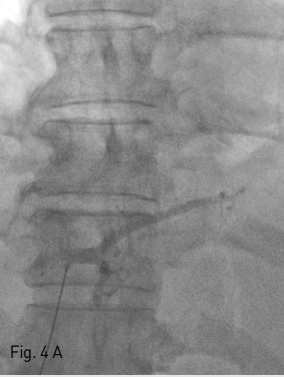

Fig 4A

Intraportal entry was confirmed by contrast injection on fluoroscopy (A).

Fig 4B

Under sonographic and fluoroscopic guidance, the needle was advanced into the left hepatic vein (B).